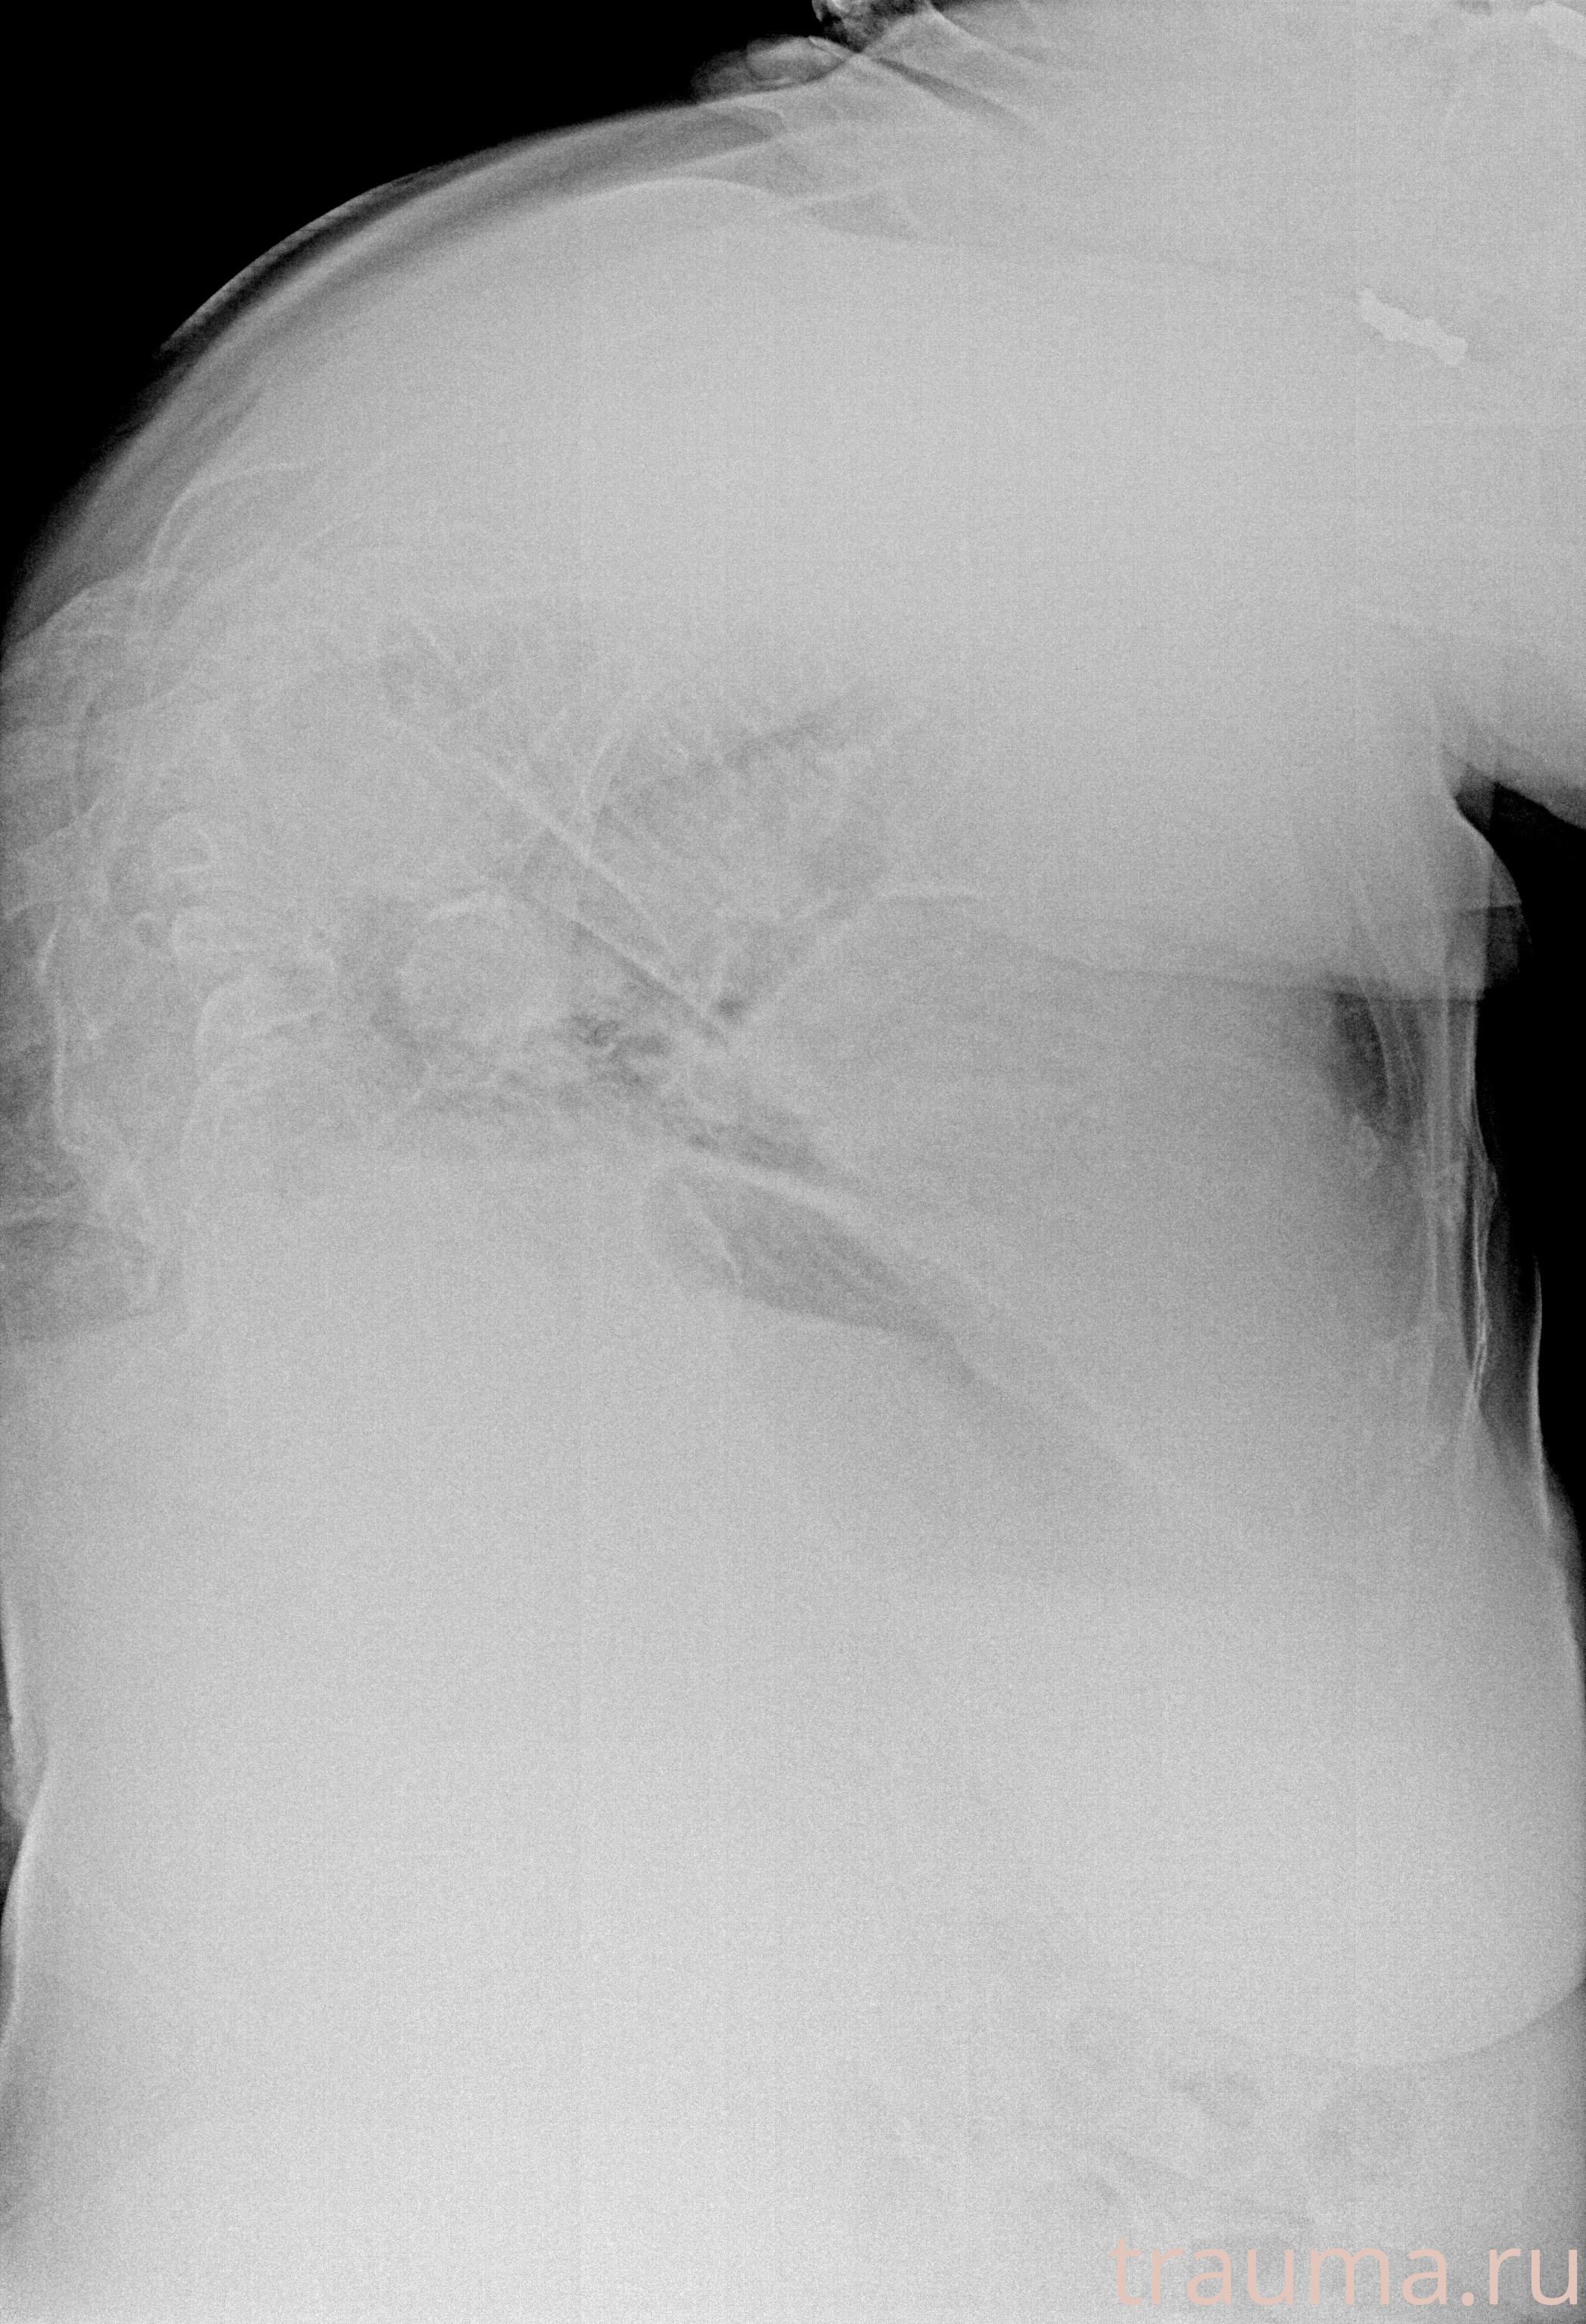

Рентген на дому: по вашему адресу приезжает врач-рентгенолог, травматолог-ортопед с мобильным рентгеновским аппаратом, проводит диагностику травмы или заболевания, делает необходимые рентгенограммы, дает рекомендации по дальнейшему лечению. Получить качественные снимки в домашних условиях возможно благодаря уникальной методике, разработанной МосРентген Центром для института  Склифосовского

при переломе шейки бедра и пневмонии от компании МосРентген Центр - партнера Института имени Склифосовского